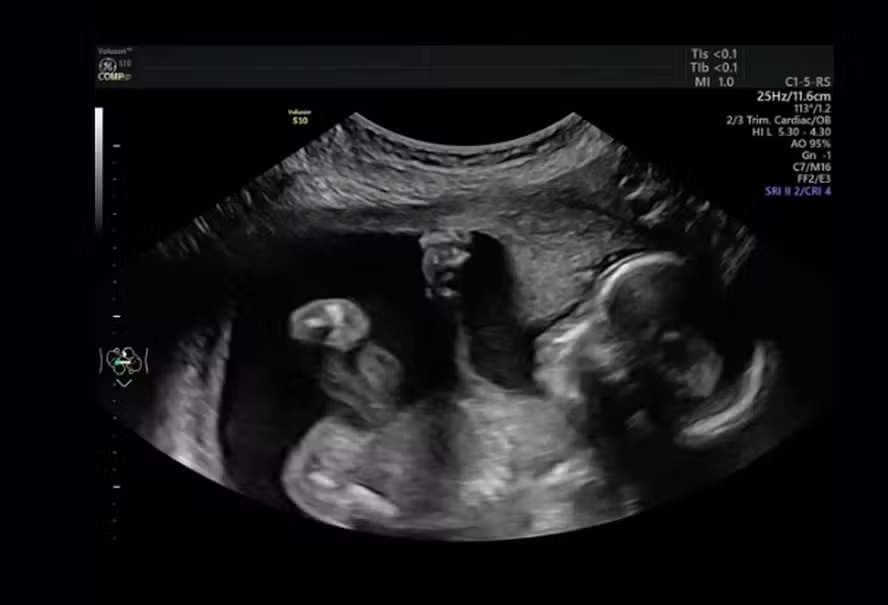

O consultório médico em Michigan (EUA) explodiu em gargalhadas quando Mara McCoy estava sendo submetida a um exame de ultrassom na 20ª semana de gravidez, em setembro.

A cena pegou a todos de surpresa. Tudo transcorria normalmente até que Pyper resolveu se manifestar: a bebê foi vista “dando um soco” na barriga da mãe. A cena, capturada pelo pai, Terrance McCoy, parecia mostrar que a pequena estava se sentindo incomodada com o exame.

Para Mara, o comportamento de Pyper reflete uma menina de “personalidade forte”.

“O vídeo mostra o quão brava ela é”, disse a mãe. “Ela estava muito ativa e pareceu me dar um soco. Ela pode ser a próxima Ronda Rousey”, continuou ela, referindo-se a uma famosa atleta de MMA.